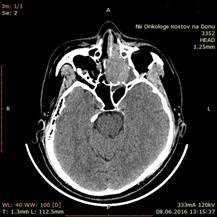

Больная З., 1948 года рождения, поступила в отделение ОГШ ФГБУ «РНИОИ» МЗ РФ 14.06.2016 г. с жалобами на затрудненное носовое дыхание слева, головные боли. При осмотре – лимфатические узлы шеи не увеличены, носовое дыхание через левую половину носа затруднено. Пальпаторно – костные структуры лицевого скелета не разрушены. При передней риноскопии – опухоль не определяется. СРКТ от 08.06.2016 г.: «Слева в области ячеек решетчатого лабиринта определяется мягкотканое образование 42х51 мм с прорастанием в верхнечелюстную и основную пазуху, полость носа (рис. 1). Легочная ткань без очагов. Патологических объемных образований в брюшной полости и полости малого таза не выявлено».

Рис. 1. СРКТ придаточных пазух носа: слева в области ячеек решетчатого лабиринта определяется мягкотканое образование 42х51 мм с прорастанием в верхнечелюстную и основную пазуху, полость носа